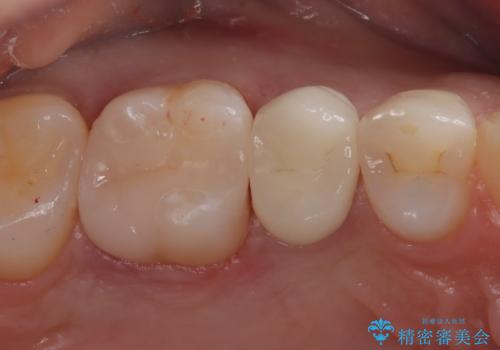

- 定期検診にて虫歯を発見したため、セラミッククラウン、セラミックインレーにて治療を行いました。

小臼歯の虫歯は歯髄に近かったため、部分的断髄法にて歯髄を部分的に保存した治療をおこなっています。